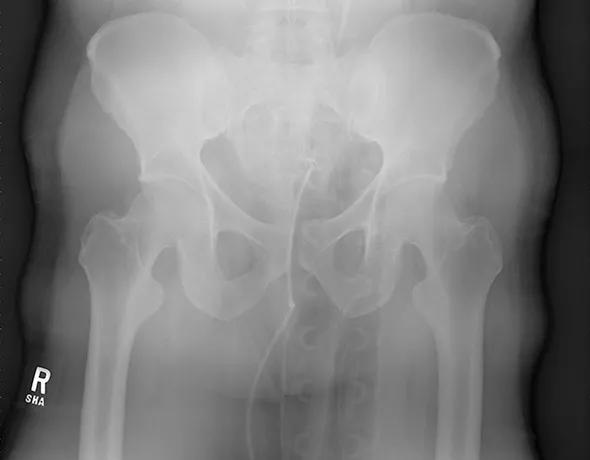

After primary and secondary surveys are complete, every work-up for a patient involved in a high-energy trauma should include an anteroposterior radiograph of the pelvis (Figure 1). Physical examination and a single radiograph can diagnose an unstable pelvic ring injury and guide patient care.

Figure 1. Anteroposterior pelvis injury film